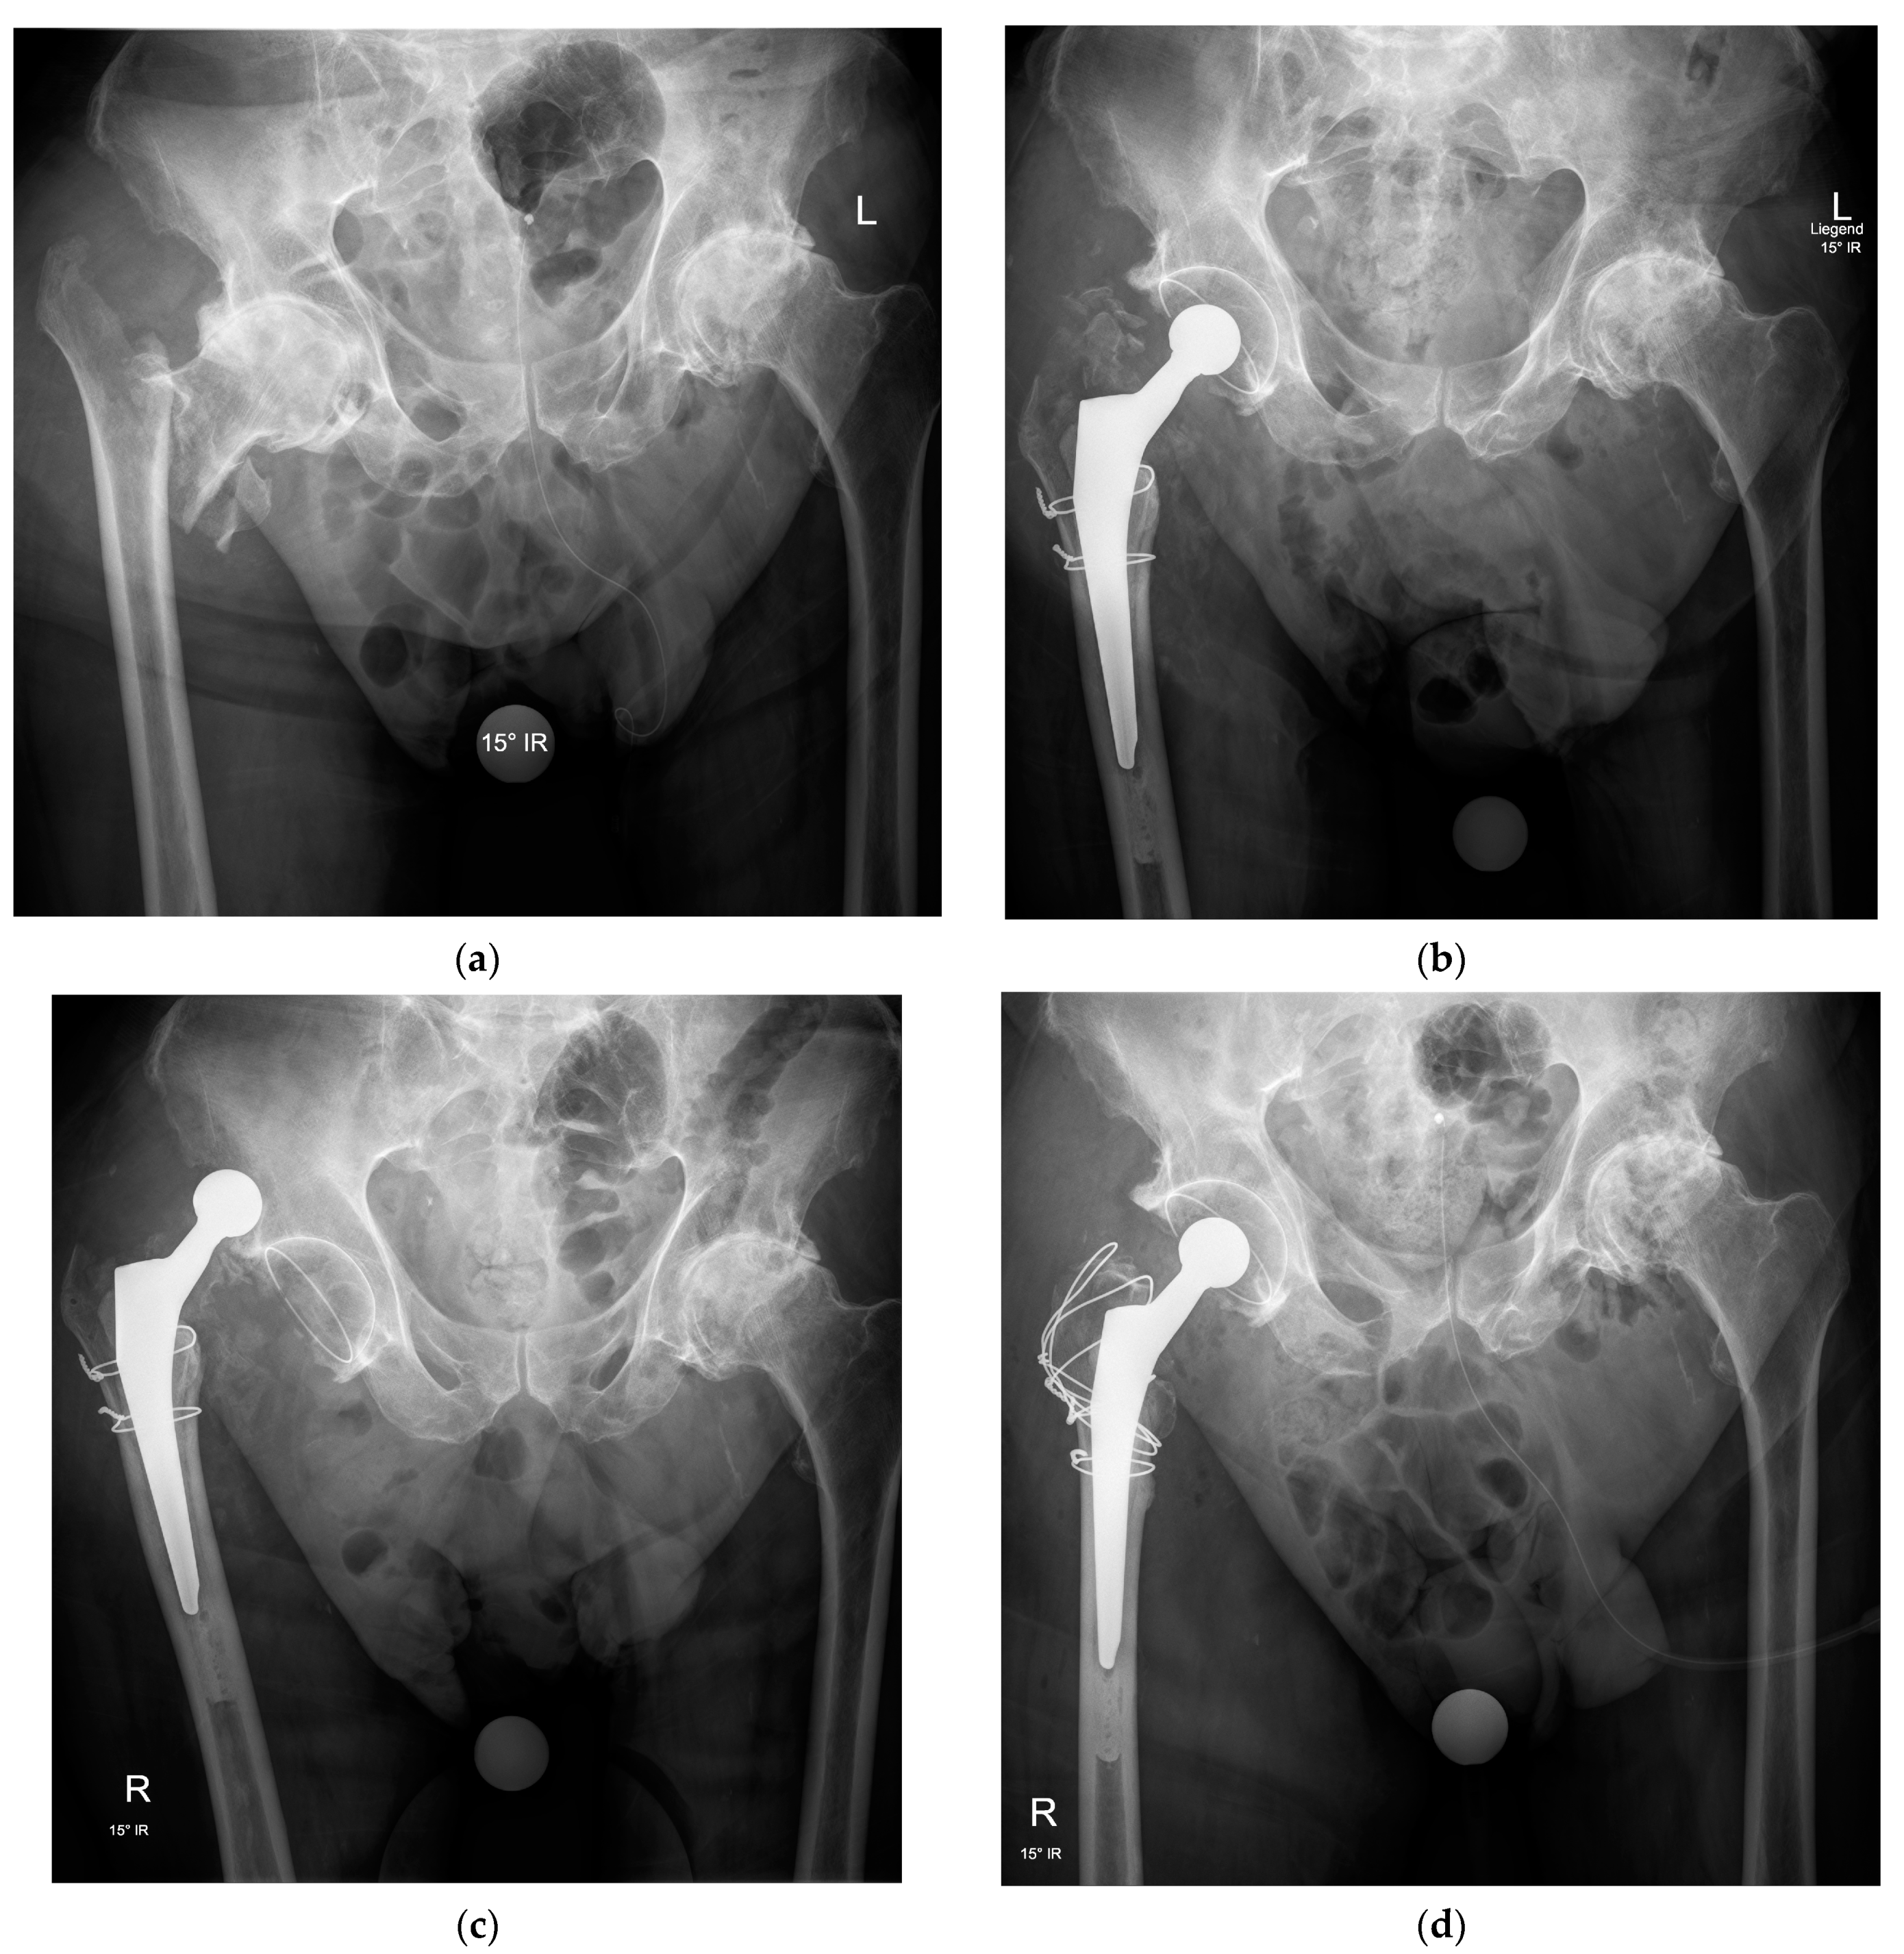

2. Indications

3.1. Surgical Approach

3.2. Implant Selection

3.3. Hip Abductor Mechanism Repair